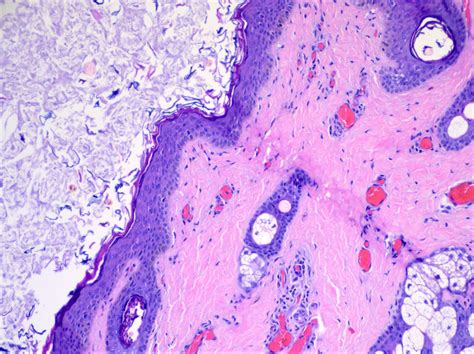

• Sebaceous Cyst: A slow-growing, benign sac beneath the skin that contains fluid or cheesy material. These can happen anywhere on the skin, including the eyelids.